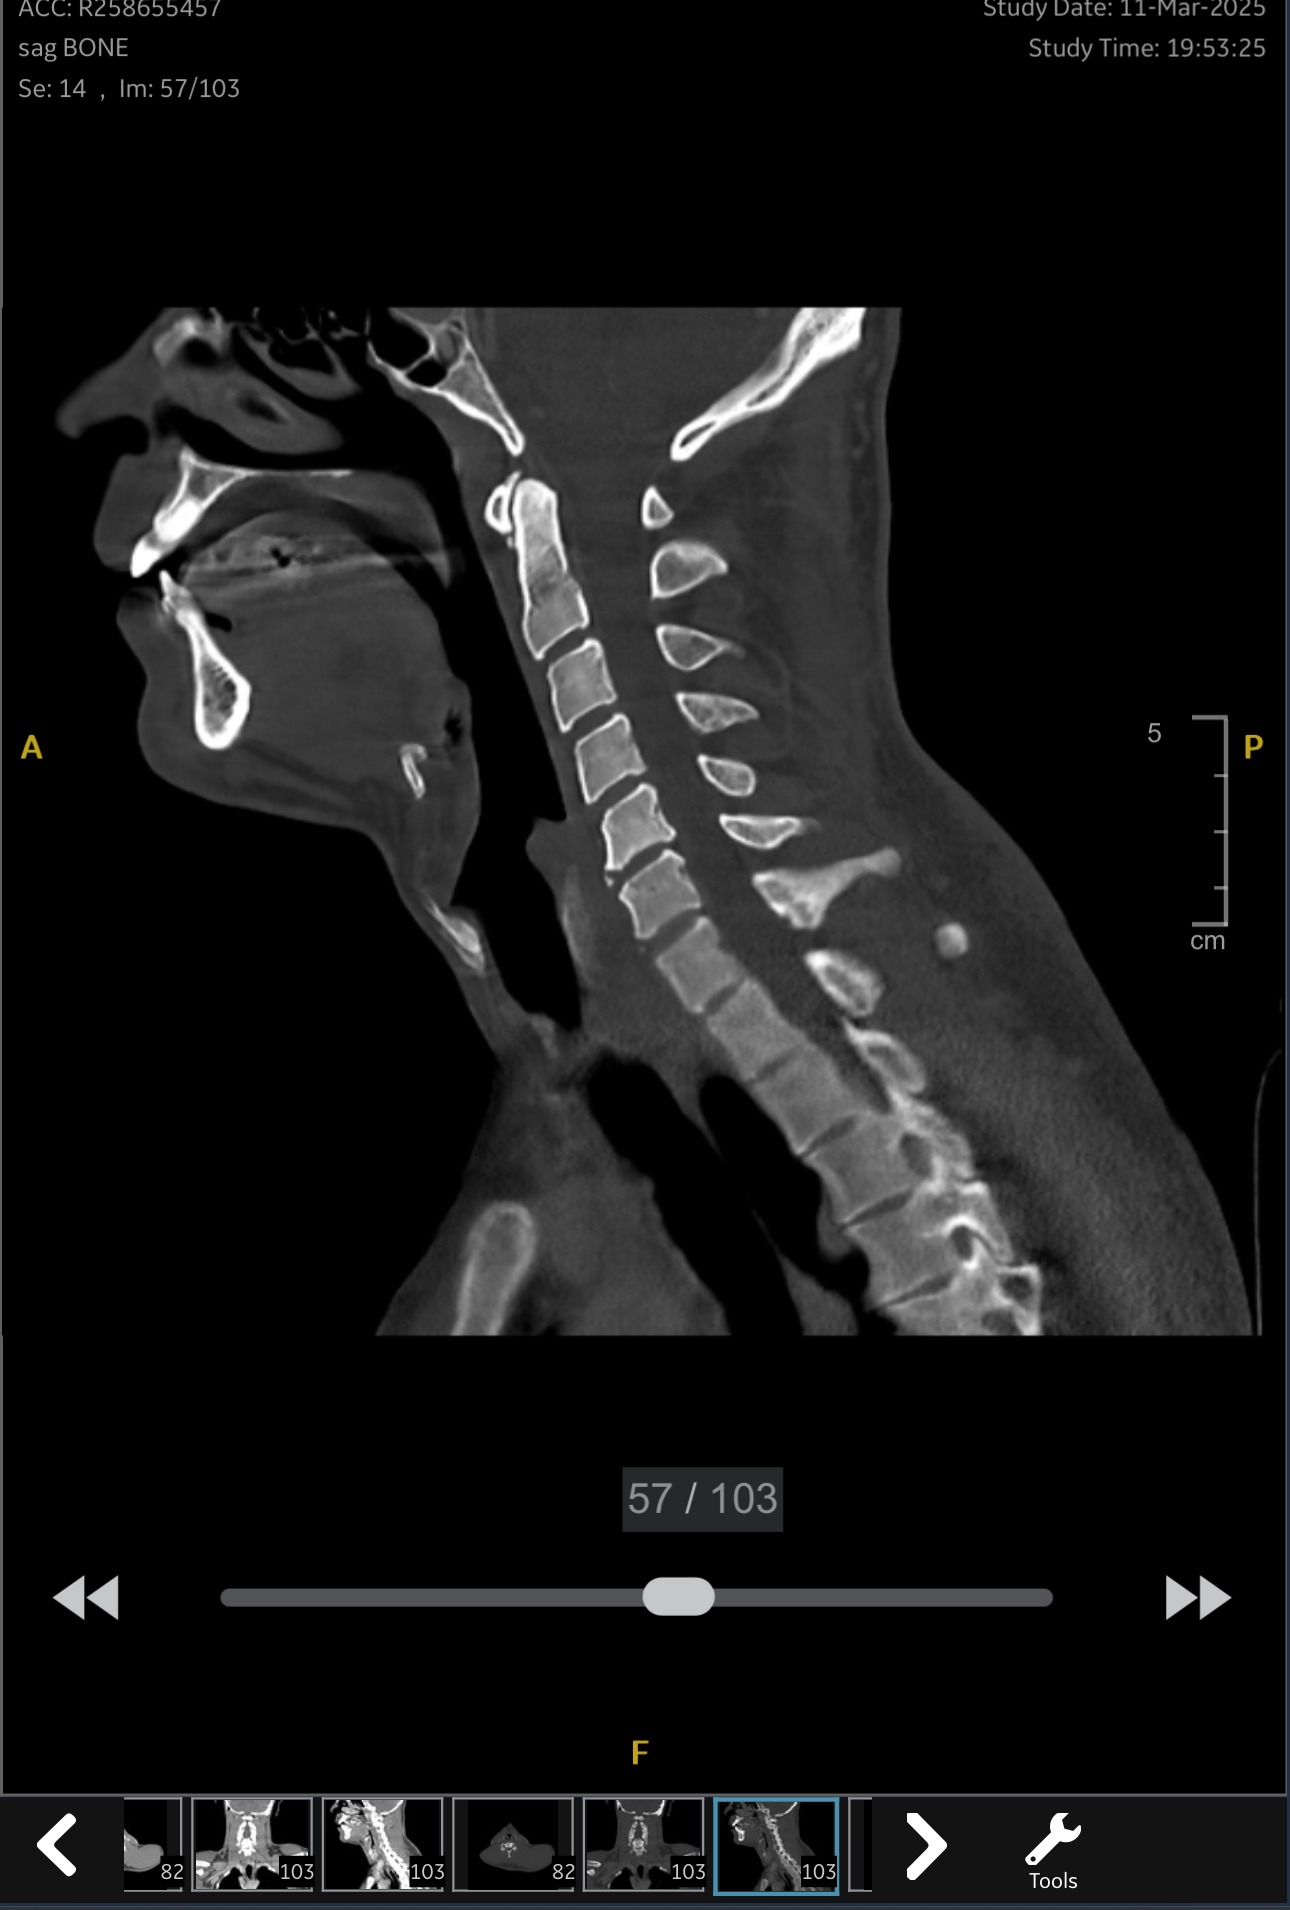

I assumed I was never going to have the same lung capacity that I had before, and that this was “my new normal”, but apparently my lungs had fully healed and the problem wasn’t a diminished lung capacity. I had scar tissue and a growth in my trachea. It seems that while I was intubated in Brazil, this caused what is known as a Tracheal Stenosis. This narrowing occurred slowly over time. Over the winter I had several chest infections, which made it worse, because of the narrowing, it also made it difficult to get infections (phlegm) out of my lungs. After months, my doctors finally decided it was best to do a tracheal resection surgery. Below are photos from my MRI/CT images and my endoscopy images.

That’s why on Tuesday April 29th I underwent a surgery to remove this Stenosis, known as a Tracheal Resection. It’s a complex surgery in a very sensitive area of the body (in my neck) where all of the major nerves and arteries exist in close proximity. During my consultation with the doctor, he indicated that this surgery will be more complex than initially anticipated considering I have 5-6cm of tissue in my trachea that must be removed, whereas typically people remove only 2-3cm of tissue. This significantly increased the likelihood complications during the surgery. The list of post-surgery complications is long as well; feeding tube, infections, severe nerve damage and other serious effects are very possible.